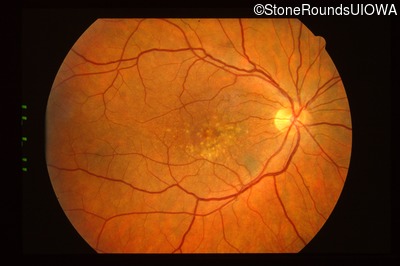

History

This 43 year old woman has experienced a gradual reduction in her central vision for the past 3 years.

Diagnosis & molecular findings

| Disease | Gene | Allele 1 variant(s) | Allele 2 variant(s) | Inheritance mode |

|---|---|---|---|---|

| Malattia Leventinese | EFEMP1 | Arg345Trp CGG>TGG | AD |